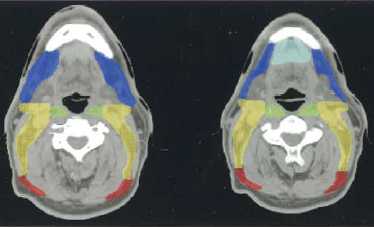

(a–l) Marked lymph nodes (LNs) with each LN group separated by color.

Light blue, submental LN (Ia);

dark blue, submandibular LN (Ib);

yellow, jugular LN (II, III, IV);

red, spinal accessory LN (V);

light green, retropharyngeal LN;

orange, parotid LN;

dark green, anterior jugular LN (VI);

pink, retroauricular/occiptal LN.